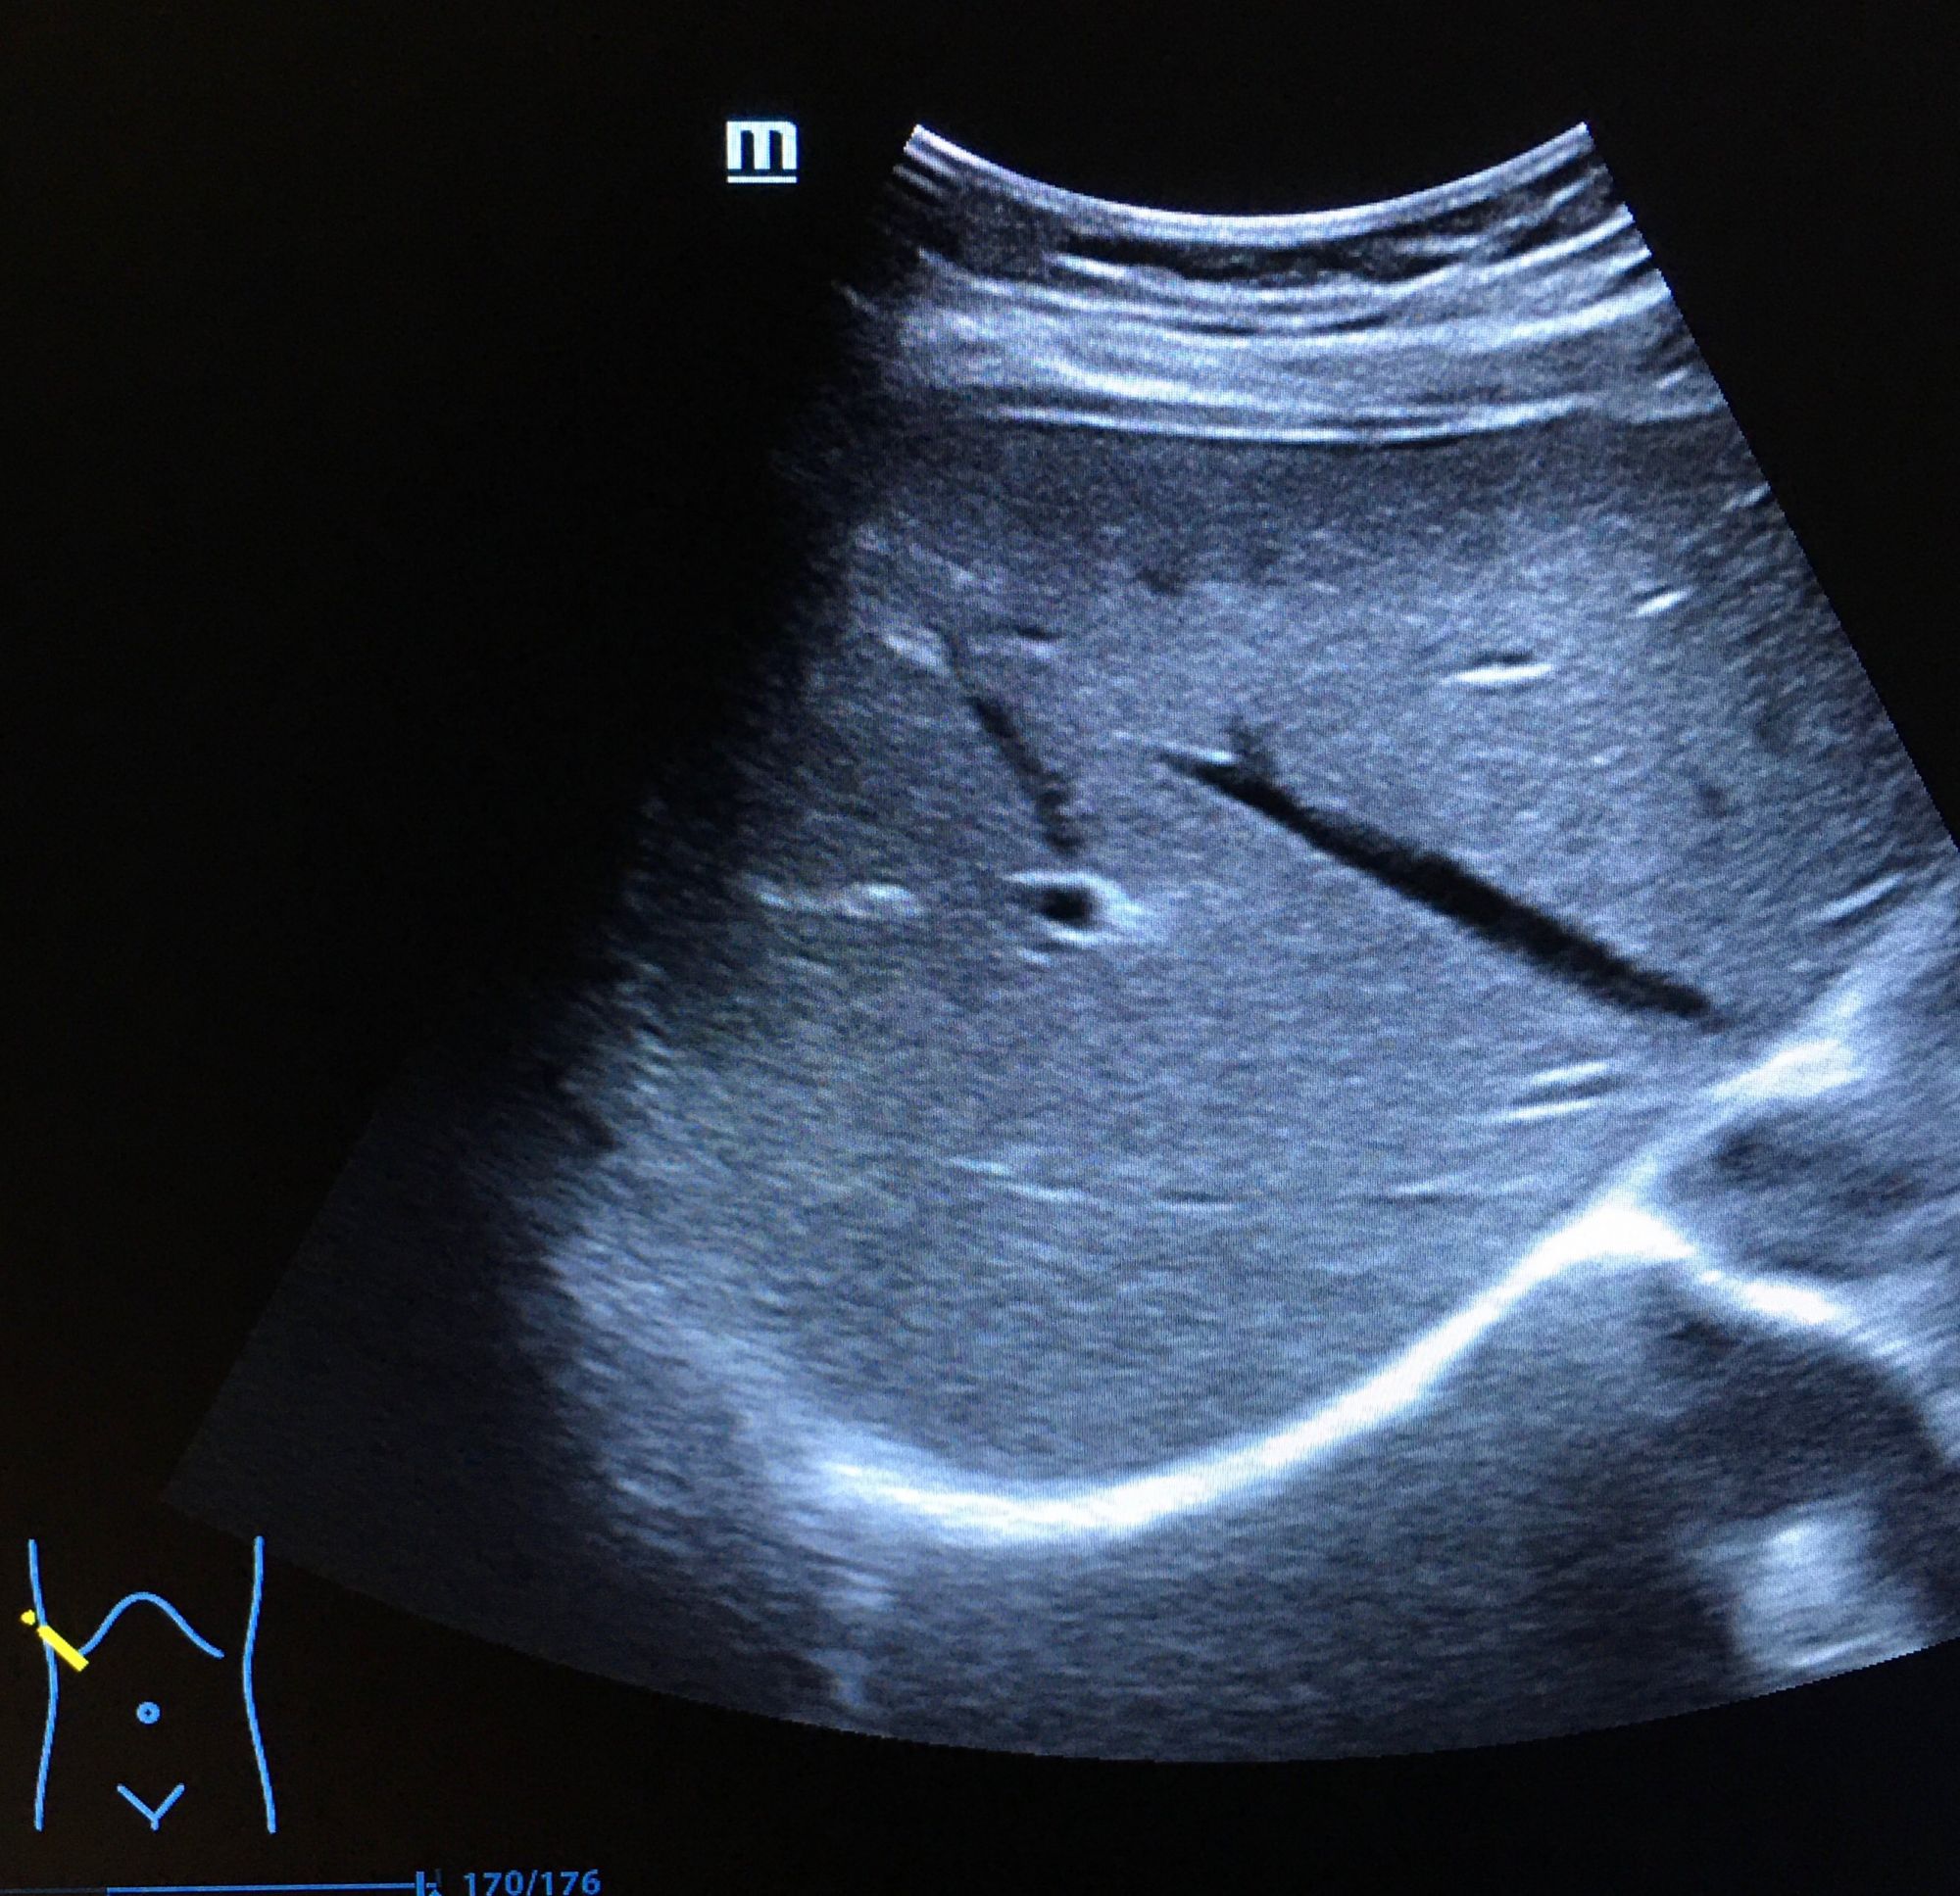

二、超聲成像

是一種基于超聲波的成像技術(shù)。超聲波在生物體內(nèi)傳播時(shí),遇到不同的組織會(huì)產(chǎn)生不同的回聲信號(hào),通過(guò)分析這些信號(hào)可以獲取生物體的內(nèi)部結(jié)構(gòu)和功能信息。超聲成像具有無(wú)創(chuàng)、無(wú)痛、無(wú)輻射等優(yōu)點(diǎn),因此在臨床診斷和生命科學(xué)研究中得到了廣泛應(yīng)用。

超聲成像